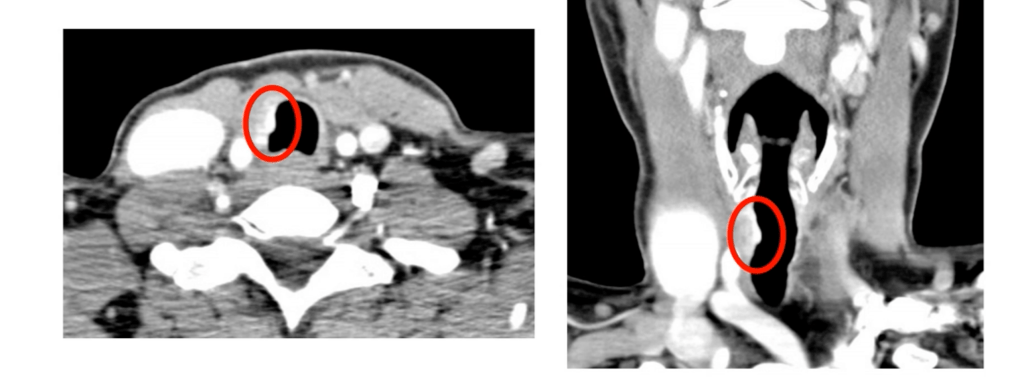

- Recurrent Laryngeal Nerve (RLN):

- If functional and partially encased:

- Consider nerve preservation via shaving

- If non-functional or fully invaded:

- Resection is advised with or without reinnervation techniques

- Postoperative vocal cord assessment is mandatory

- Statement 2-A:

- RLN encased, ipsilateral vocal cord (VC) paresis / paralysis:

- Resection is indicated (consensus)

- Statement 2-B:

- RLN encased, ipsilateral bilateral normal VC function:

- Tumor may be shaved off to spare the RLN, as long as all gross disease is removed (consensus)

- Statement 2-C:

- RLN encased, contralateral VC paretic / paralyzed:

- Tumor may be shaved off so that the RLN is spared (consensus)

- If the nerve is sacrified RLN reconstruction is advisable or thyroplasty or cord injection.